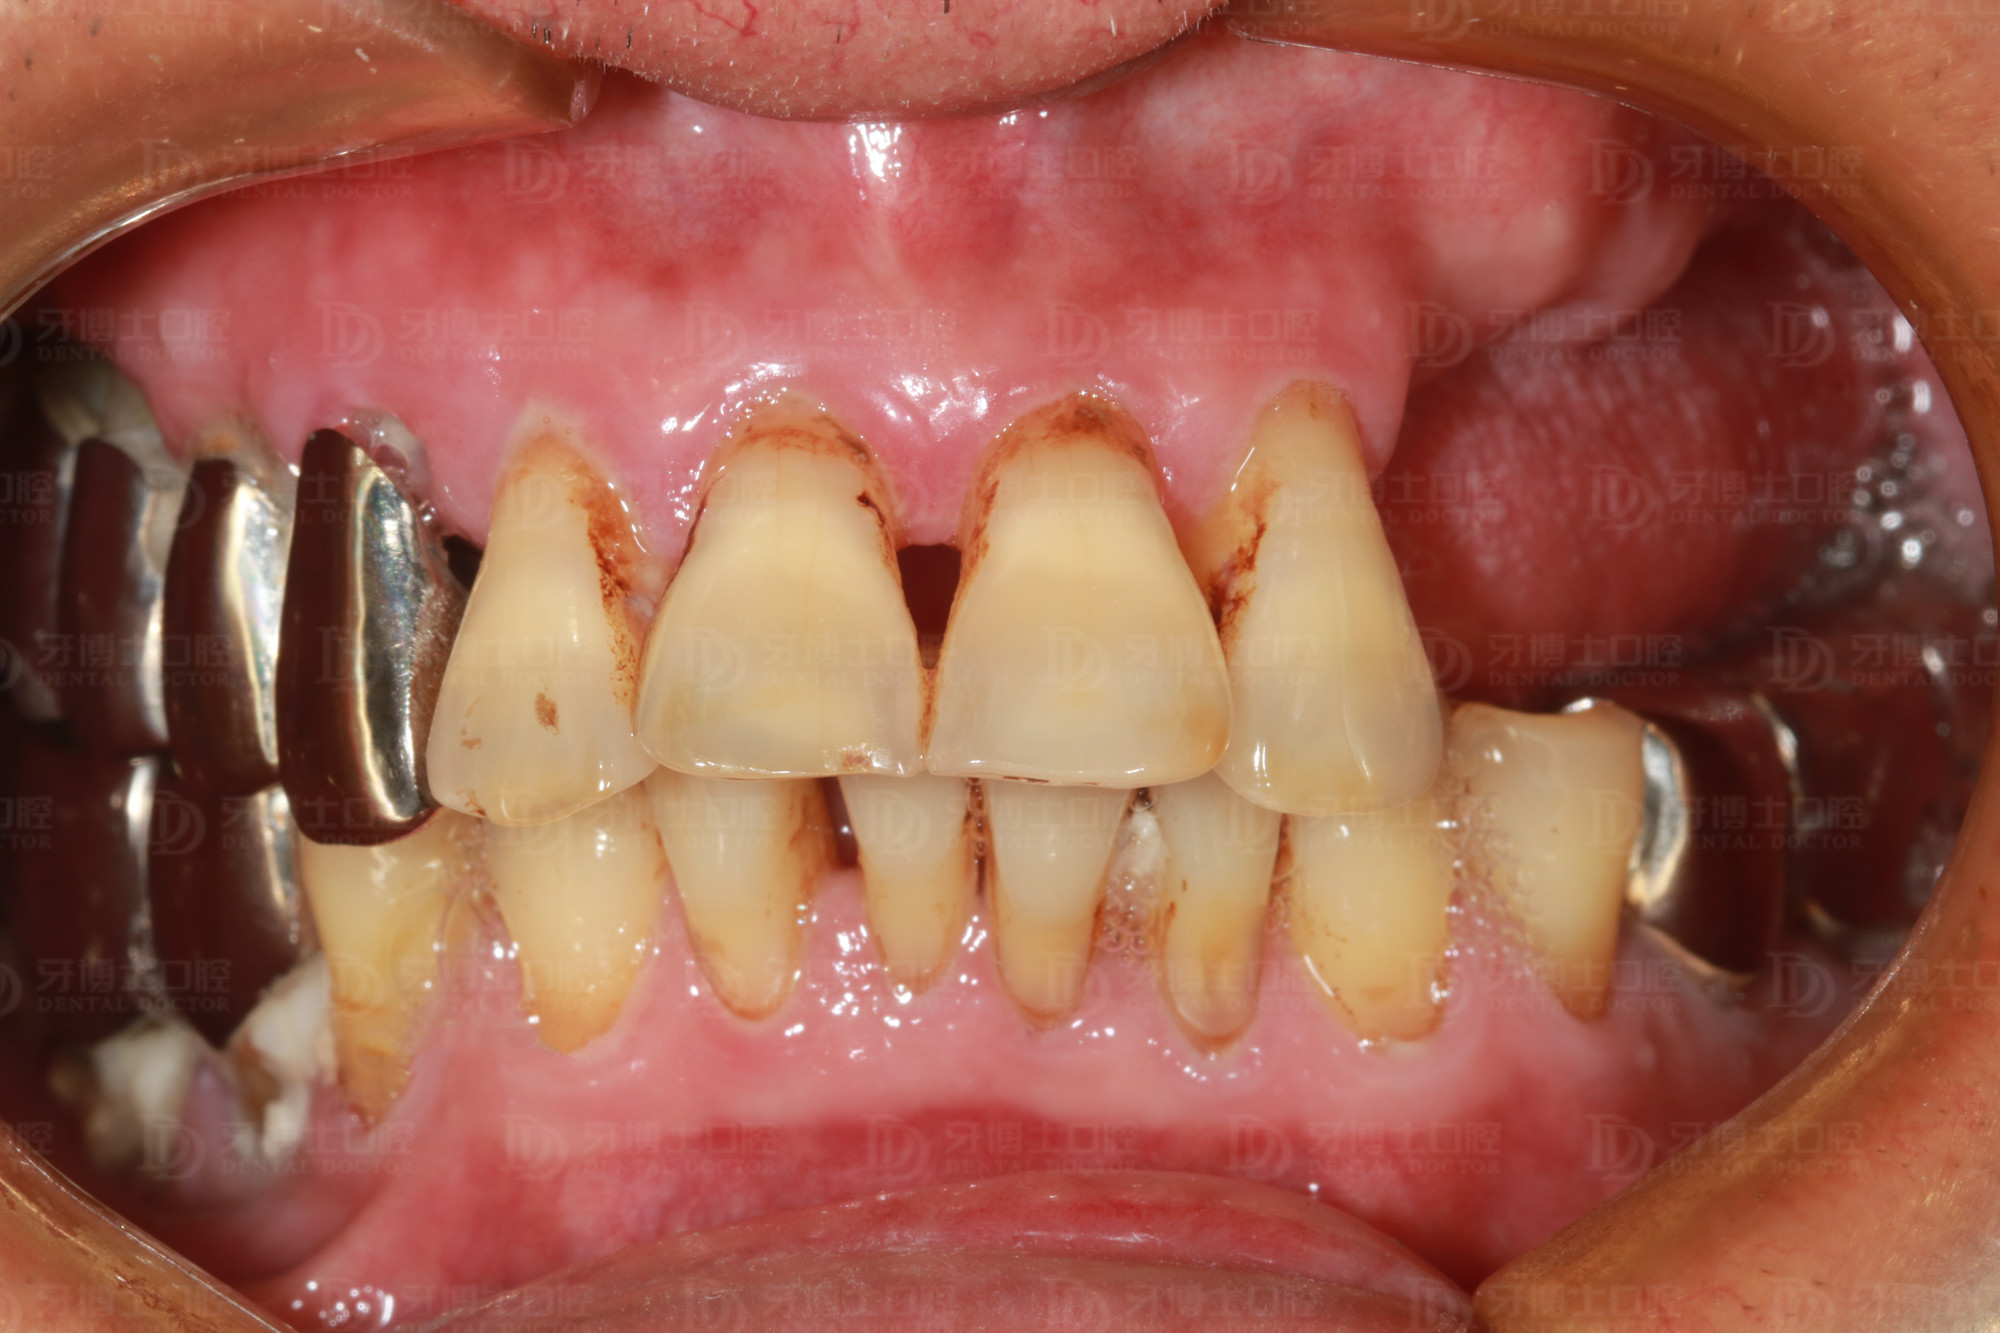

年近七旬的周老爷子(化名)牙齿缺失多年,上排牙只剩4颗前牙。前些年做的一侧不锈钢牙松得非常厉害,因为长期用那一侧牙咀嚼,导致牙齿的牙根全部咬坏掉了,医生开玩笑说“你这牙很脆弱了,打个喷嚏就会掉下来”。

据医生介绍,像周老这种情况在临床上很常见,后边大牙缺失,咀嚼时前面三颗牙带后面两颗牙,咀嚼时间久了,形成杠杆作用,加上前面牙齿又负荷过重,牙根就全部断掉了,只能拔除。

种牙前